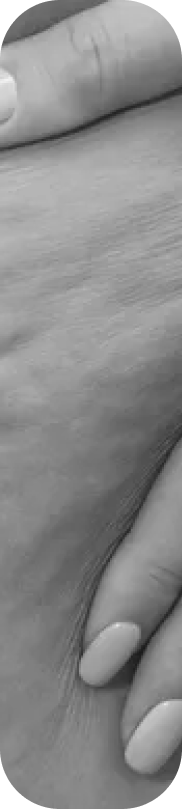

El lipedema no es solo una cuestión estética. Es una condición médica progresiva que causa acumulación anormal de grasa en piernas y brazos, dolor crónico, pesadez extrema y, en muchos casos, vergüenza e incomprensión. Muchas mujeres pasan años sin diagnóstico, sintiéndose frustradas y sin respuestas.